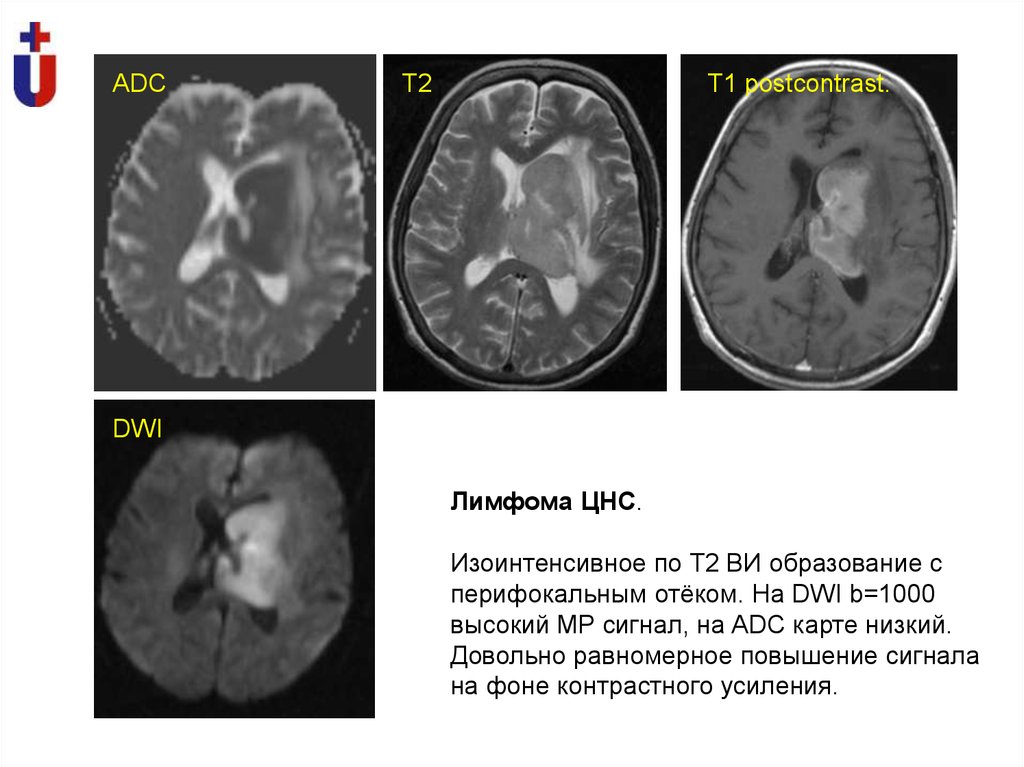

ADC

Т2

Т1 postcontrast.

DWI

Лимфома ЦНС.

Изоинтенсивное по Т2 ВИ образование с

перифокальным отёком. На DWI b=1000

высокий МР сигнал, на ADC карте низкий.

Довольно равномерное повышение сигнала

на фоне контрастного усиления.